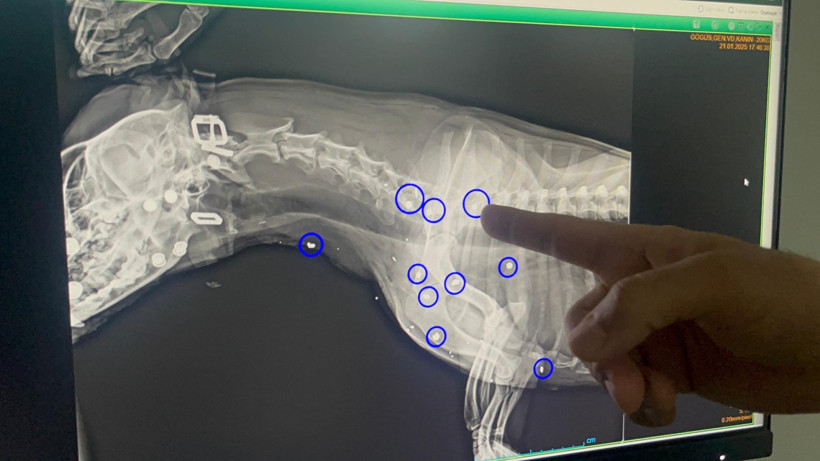

Ünlü "Ertesi gün röntgeni çekildiğinde de 12 yerinde saçma yaraları olduğunu gördük. Hayati organlara çok yakın olduğu için saçmaları ne yazık ki alamadık. Şu anki süreçte de kalbinde bir büyüme olduğu için ne yazık ki anestezi uygulayamıyoruz, sonraki süreçte kurşun yaralarından dolayı zehirlenme var mı diye durumu mutlaka değerlendirip test ve kontrollerini yapacağız" dedi.